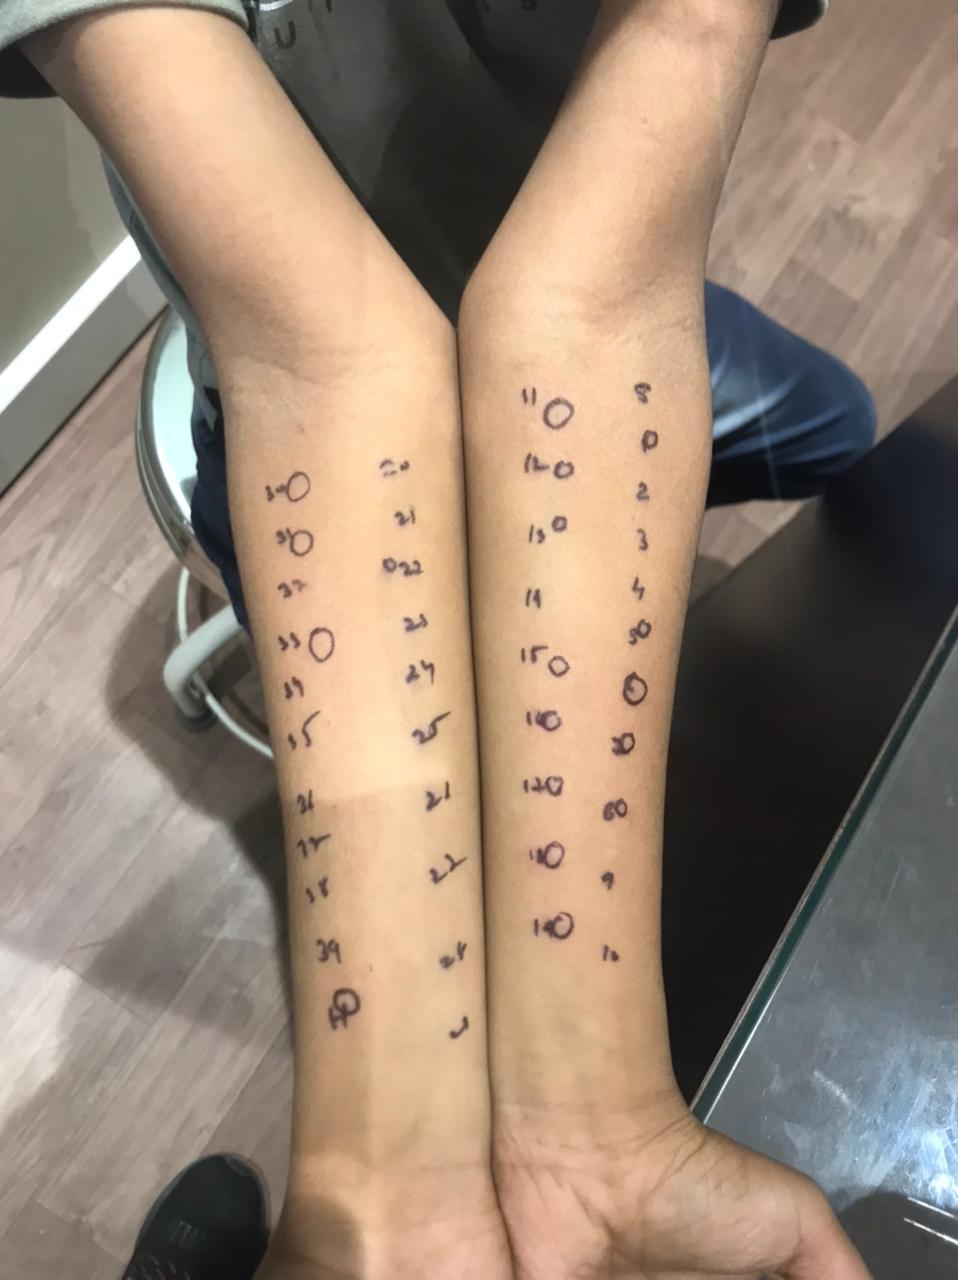

Dr. Shweta Diagnostic & Child Care Centre

Expert Care in Fetal Medicine, Pediatrics & Diagnostics

Your trusted destination for compassionate and advanced healthcare — from pregnancy to childhood and beyond. We specialize in fetal medicine, pediatric care, and precision diagnostics, all under one roof for your family’s complete wellness.